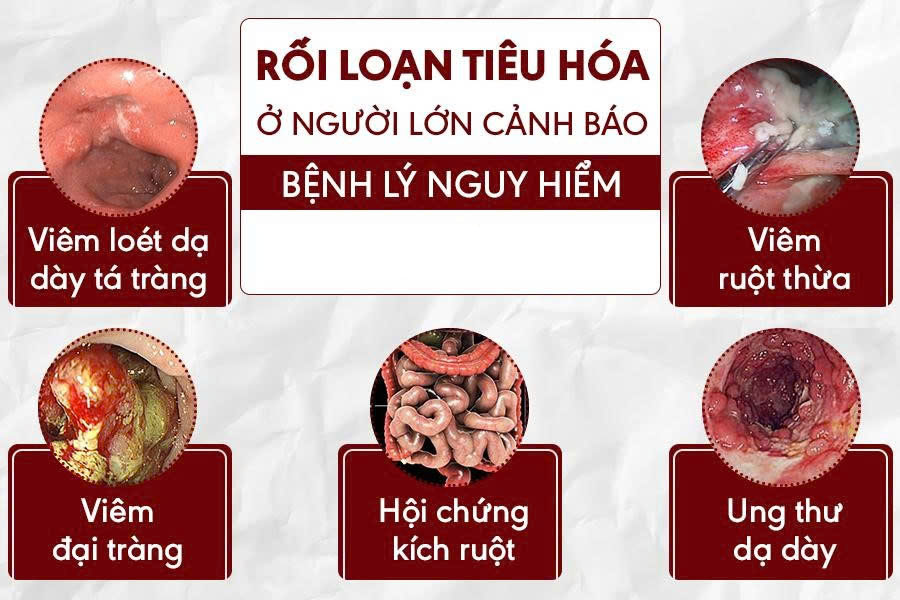

Người táo bón thường đi đại tiện ít hơn 3 lần mỗi tuần . Khi phân ở lại quá lâu trong đại tràng, nước trong phân bị hấp thụ gần hết, tạo phân trở nên khô cứng. Điều này thường liên quan đến chế độ sinh hoạt hoặc các yếu tố khác làm suy giảm chức năng tiêu hóa. Nhiều nghiên cứu cho thấy rằng táo bón là biểu hiện ban đầu của nhiều bệnh lý nguy hiểm sau này.

Các nghiên cứu gần đây đã chỉ ra rằng, nếu bạn đang bị táo bón kéo dài, đừng chủ quan. Vậy thì táo bón có nguy hiểm không? Câu trả lời là Có. Táo bón không chỉ gây khó chịu, ảnh hưởng đến sinh hoạt hàng ngày mà còn tiềm ẩn nhiều nguy cơ đối với sức khỏe nếu không thể xử lý kịp thời. Dưới đây là những lý do làm bạn không nên xem nhẹ táo bón: